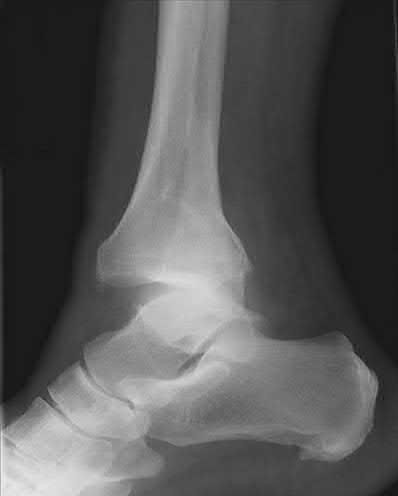

A 25-year-old female is involved in a motor vehicle collision. She presents with the isolated injury seen in Figures A through D. Her leg is swollen but her skin is intact. She has no clinical signs of compartment syndrome. Which of the following treatment options will allow for maintenance of fracture alignment and minimize the risk of soft tissue complications?

The patient presents with a closed distal third metaphyseal-diaphyseal distal tibia fracture with simple intra-articular extension. Immediate intramedullary nailing along with percutaneous fixation of the articular component provides appropriate restoration of length, rotation and alignment and minimizes the risk of wound complication.

Displaced distal third tibia fractures may be associated with simple intraarticular extension. Operative treatment of intra-articular distal tibia fractures has historically been performed with open reduction and internal fixation. Early open reduction and plate fixation of pilon fractures has been associated with high rates of infection and wound complication. In select patterns with simple articular extension, percutaneous screw fixation and medullary nailing may provide appropriate reduction with minimal soft-tissue risk.

Marcus et al. evaluated the outcomes of immediate intramedullary nailing and percutaneous fixation of simple intra-articular distal tibia fractures (AO/OTA 43 C1 and C2). The authors found excellent rates of union and alignment, however caution against broad application of this technique until more rigorous randomized studies can be performed.

Sirkin et al. retrospectively evaluated the results of a staged approach to management of intra-articular distal tibia fractures with temporary bridging external fixation followed by open reduction and internal fixation (ORIF). The authors found decreased rates of wound complication and infection compared with prior studies.

Figures A and B demonstrate a distal third tibial shaft fracture with simple intra-articular extension. The axial and coronal CT cuts in Figures C and D further clarify the articular injury. Illustrations A and B demonstrate a comminuted distal third tibial fracture with simple intra-articular extension. Illustrations C and D are fluoroscopic images of the same injury after intramedullary nailing and percutaneous fixation of the articular component.